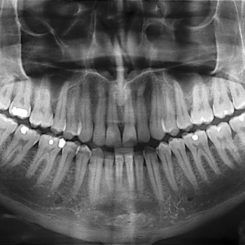

If you’ve ever stood on a circular thing with your chin on a little platform and been told to stand still for a few seconds while a machine spun around your head, you’ve had a panoramic X-ray. This is the most common type of extraoral (outside the mouth) X-ray.

Panoramic X-rays show the entire mouth in one image. In them, we can see incoming adult teeth and wisdom teeth, including impacted ones, which is how we can determine whether there is enough room for them and if they’ll come in without any extra help. This type of X-ray also makes it easier to detect abscesses, tumors, and cysts.